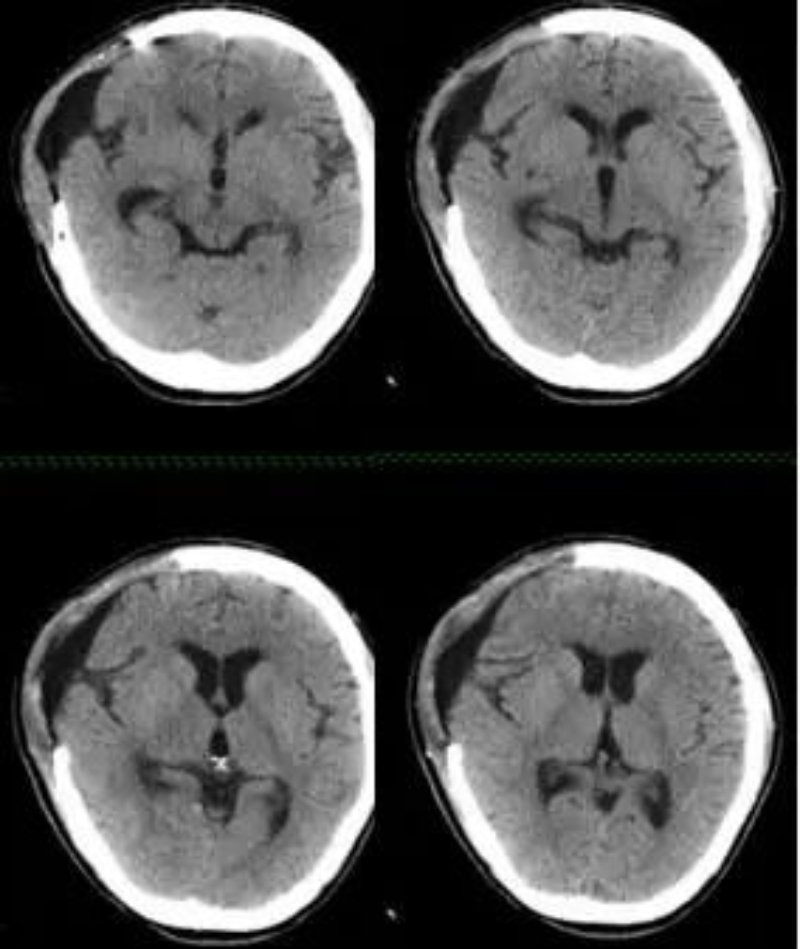

△ 患者术前CT片。

王女士入院时右侧额颞顶部大量硬膜下血肿,值班医生贺新平副主任医师立即将该患者病情汇报黄小山主任医师,科室立即组织讨论,综合考虑该患者为年轻女性,近期透析过程中有使用肝素抗凝,为减少创伤,首先选择右侧额颞顶部硬膜下血肿软通道置管引流术。手术过程顺利,置管位置良好。

△ 置管引流术后CT。

因患者透析过程中有使用肝素抗凝,虽引流管位置良好,但因患者凝血功能异常,合并有新鲜出血,考虑病情危重同时需要血液透析治疗,急诊请肾内科、重症医学科会诊后,经综合讨论意见后转我院重症医学科监护治疗,并行床边CRRT治疗。